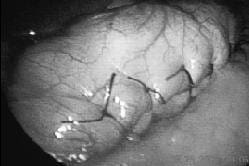

Se coloca la sonda contra la curvatura menor y se avanza hasta la región prepilórica. Se colocan puntos en seda cero separados entre la pared posterior gástrica y la anterior, y se crea así una plicatura gástrica desde el fondo gástrico, introduciendo el tejido gástrico hacia su propia luz. En su inicio en el ángulo de Hiss, la sutura debe quedar ajustada totalmente a la sonda oro-gástrica; hay que recordar que, al no haber resección de tejido gástrico y éste estar en su propia luz (imbricado), existe una mayor restricción de la que suponemos al mirar el remanente gástrico en su porción exterior, fácilmente valorable al movilizar la sonda y palpar con las pinzas laparoscópicas. Los puntos se extienden hasta los 3 cm del píloro y así creamos una restricción amplia (figuras 1-3).

FIGURA 2. Surset gástrico de Sales; se observa la plicatura en toda su extensión y la capacidad gástrica final